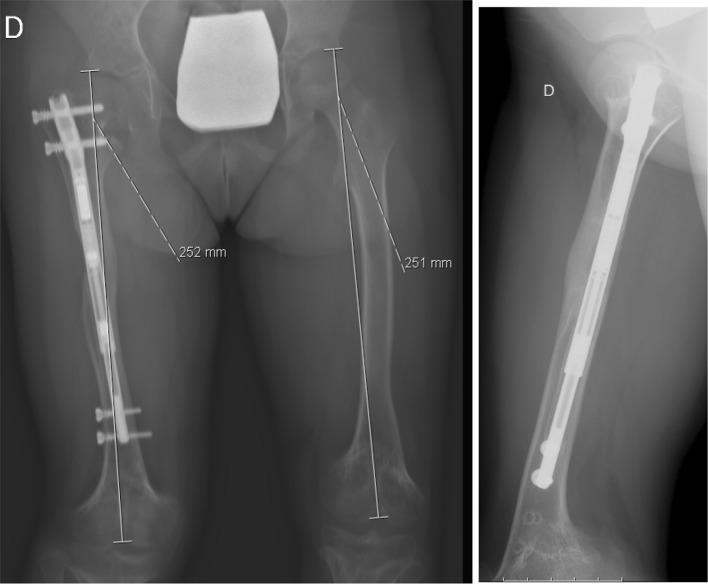

The authors present a case in which the limb lengthening has been performed in consecutive lengthening periods using the same nail. The nail was extended and retracted by altering the settings on the external remote control as well as accurately setting the rate of distraction.

After two consecutive femoral lengthening with the same PRECICE nail, the patient no longer has a significant lower limb length discrepancy and patient satisfaction was high. During this clinical case, we were not confronted with any type of complications.

作者呈现了一个病例,其中使用同一根钉子在连续的延长阶段进行肢体延长。通过改变外部遥控器的设置以及精确设定牵张速率来使钉子延长和回缩。

使用同一根PRECICE钉子连续两次进行股骨延长后,患者双下肢长度差异不再显著,患者满意度较高。在这个临床病例过程中,我们未遇到任何类型的并发症。